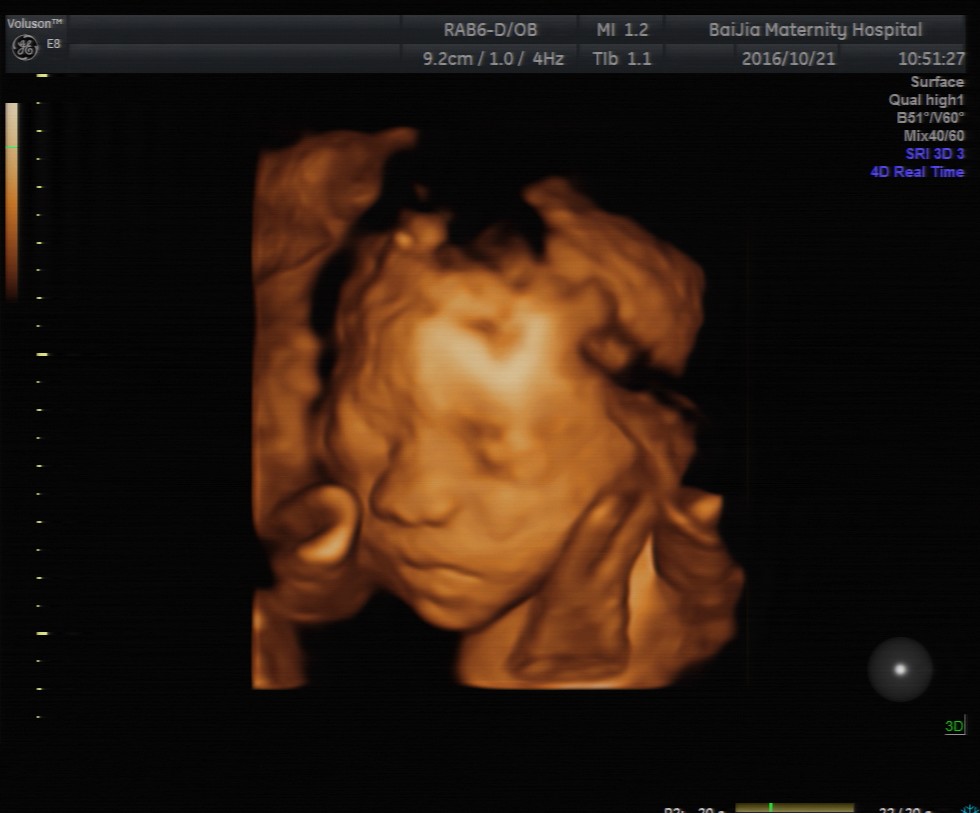

四维彩超能直接观察到胎宝宝发育及在宫内的活动情况,这让很多孕妈咪都很期待做四维彩超检查,但清晰的四维成像对孕周有着严格的要求, 那么, 上海做四维彩超的最佳时间是多

四维彩超能直接观察到胎宝宝发育及在宫内的活动情况,这让很多孕妈咪都很期待做四维彩超检查,但清晰的四维成像对孕周有着严格的要求, 那么,上海做四维彩超的最佳时间是多少周呢?

理论上来讲,孕20—24周是做四维彩超的最佳时间,这个时期是胎儿的快速发育时期,胎儿的基本结构已经形成。同时,适中的胎儿大小及羊水量,给胎儿提供了较大的活动空间,有利于全方位观察胎儿的活动状态。

除了观察胎儿的活动情况,孕中期对胎儿做四维彩超的主要目的是筛查胎儿结构畸形。